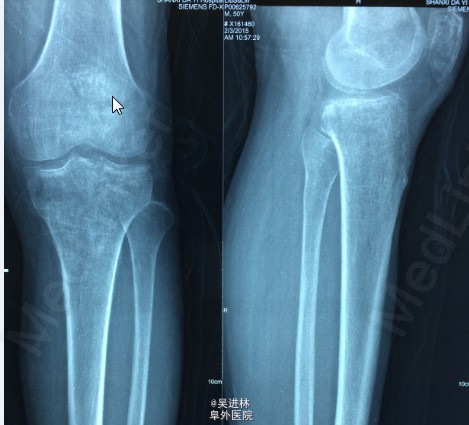

患者6个月前无明显诱因出现左膝关节内侧间隙疼痛,就诊于当地医院,诊断为骨坏死(骨髓水肿易误诊为骨坏死),行左股骨内侧髁开窗病灶清除术。一月前无明显诱因再次出现左膝关节外侧间隙疼痛,无法行走,站立及上下楼梯,无发热,无腰痛,无下肢肿胀,我院诊断为“骨髓水肿”。骨髓水肿发生于单髁是比较少见的,通常累及整块骨头,这个病人不仅在单髁发生骨髓水肿,而且奇怪的是,左侧髁水肿好了之后,外侧髁侧又出现了水肿。